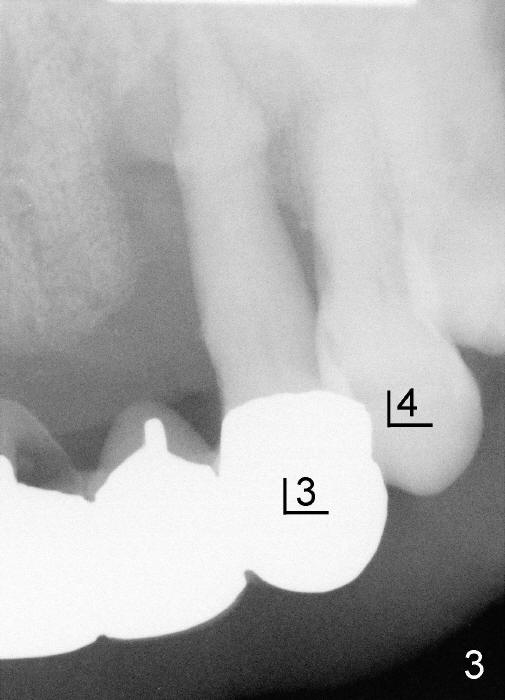

原来这个前臼齿有三个牙根(图四远中颊侧观):近中颊侧(MB),远中颊侧(DB),鄂侧(P),颊侧两个根之间有凹陷:颊侧(图五近中颊侧观:箭头),鄂侧(图六近中鄂侧观:*),凹陷处以及根分叉处充满牙槽骨,所以拔牙困难。

这种前臼齿牙根分布有点象上颌磨牙。颊侧两个根近远中宽度比鄂侧根宽(图四至图六),这个现象同样表现在X光片上(回到图一,图二),图七,图八是图一,图二放大,显示颊侧根(MB和*)比鄂侧根(P)宽,图八红线代表颊侧根根尖,黑线鄂侧根根尖。